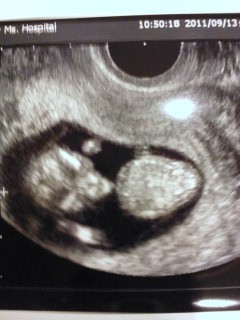

CRL37.0mm 心拍152~171(大体10w6dの大きさ)。

手足が確認できました。エコー見てるときに寝返りをうって、くるくる前向いたり背中向いたりしていて、旦那が感動して涙してました。やっと母子手帳を貰いに市役所に行けます。

CRL:38.6mm BPD:15.5mm

とても標準的な大きさです☆★

両手・両足を素早く曲げ伸ばししていて、見た瞬間シャドウボクシングしてると思いました。

丁度仰向けでエコーが撮れてラッキーでした~♪